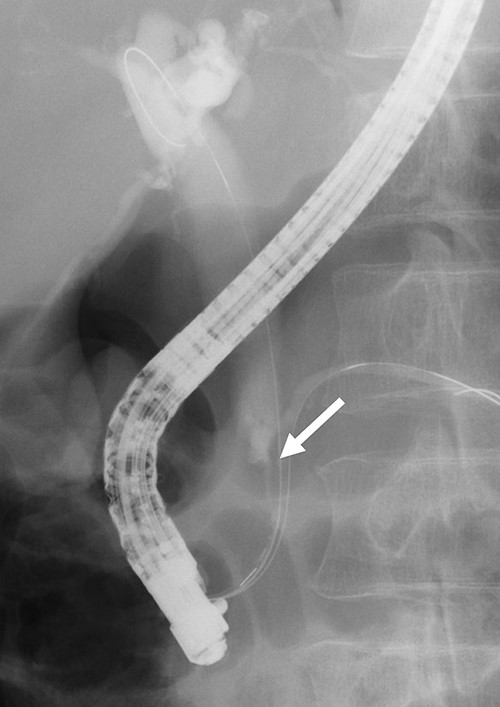

Contrast-enhanced computed tomography (CT) revealed wall thickening and stricture of the distal common bile duct (CBD) (Fig. 1). Dilation of both the intrahepatic bile ducts and the common hepatic duct was also observed (Fig. 2). No lymph node or distant metastases were observed. Endoscopic retrograde cholangiopancreatography revealed irregular stenosis in the distal CBD (Fig. 3). Thereafter, biliary drainage and brush cytology were performed, and an adenocarcinoma was detected.

ERCP revealed irregular stricture of the distal CBD (arrow); brush cytology was performed at the same time.